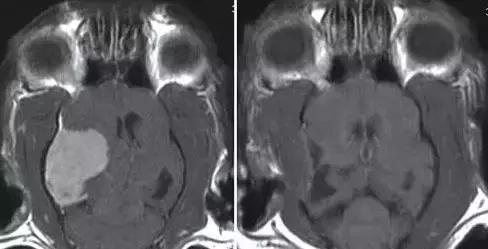

左图:MRI扫描正常的猫大脑

右图:疑似癫痫诱发脑损伤(海马坏死)的猫大脑(白箭头所指)

图中患猫表现为急性全身性癫痫发作和行为改变,包括攻击、流涎和方向迷失